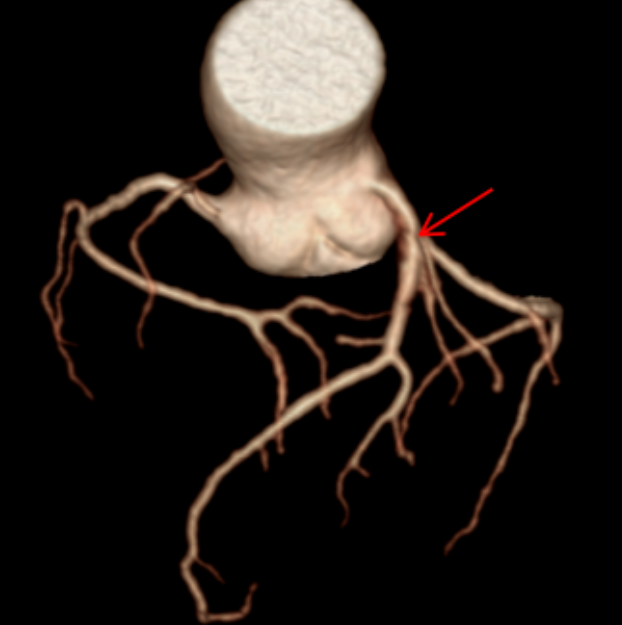

随即,张老先生被安排进行了一项关键检查:冠状动脉CT血管成像(CCTA)。对于一位81岁高龄、心律不齐且难以长时间屏气的老人来说,传统的CT扫描可能因呼吸运动和心跳产生伪影,导致图像模糊、诊断困难。然而,这次检查使用了——GE 256排宽体探测器CT。其核心优势在于“快”与“宽”:探测器覆盖范围宽,仅需0.3秒的极短扫描时间,就能完成心脏区域的完整数据采集。这意味着患者可以自由呼吸,无需刻意屏气,并且高速扫描能“冻结”心跳,极大削弱了心律不齐对图像质量的干扰,从而获得清晰、可靠的心脏血管图像。

CT表现:冠状动脉粥样硬化,左冠状动脉前降支近端中度狭窄,左冠状动脉前降支心肌桥形成。

正常情况下,血管走在心脏表面,收缩舒张自由;而当血管被心肌“桥”覆盖时,心脏每次收缩挤压,都可能短暂压迫这段血管,影响远端的血液供应。狭窄加上心肌桥的叠加效应,很好地解释了他为何出现胸闷、胸痛(心绞痛)和心律不齐的症状——心肌正在发出“缺血”的求救信号。

冠状动脉CTA已成为筛查和诊断冠状动脉疾病的无创性“金标准”之一。它通过静脉注射对比剂,利用CT快速多层扫描和三维重建技术,直观展示冠状动脉的走行、管腔狭窄程度、斑块性质(如钙化斑块或软斑块)以及血管壁的情况。对于像张老先生这样的病例,CTA不仅能精准测量狭窄百分比,还能识别心肌桥这一解剖变异,评估其与狭窄的相互影响,为临床制定治疗方案(是药物保守治疗,还是需要介入支架或外科搭桥)提供了至关重要的参考。报告中提到的宽体探测器技术,代表了当前CT发展的前沿方向,特别适用于心率快、心律不齐、不能配合屏气或身体虚弱的患者,极大地拓宽了心脏CT检查的适用人群和诊断成功率。